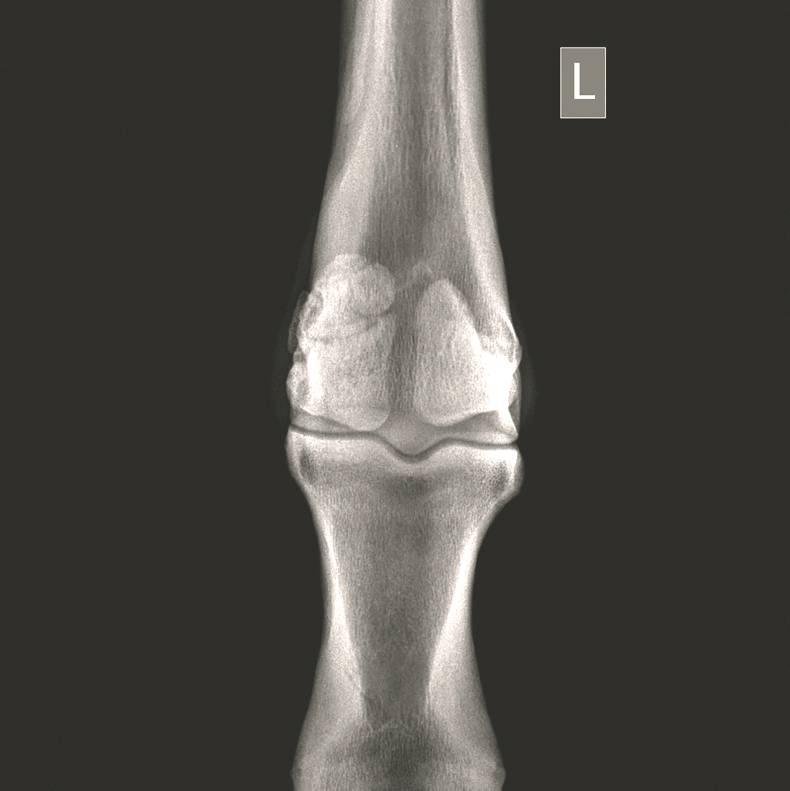

WITH the sales season in full swing, a set of X-rays of a horse involves usually a standard set of 36 views of the fetlocks, knees, hocks and stifles.

A huge number of abnormalities can be found on X-rays, such as sagittal ridge Osteochondritis Dissecans (OCD) defects in the front fetlocks; fragments off the back of the pastern bone; bone cysts in the ulnar carpal bone; and ‘spurring’ in the hock joints.